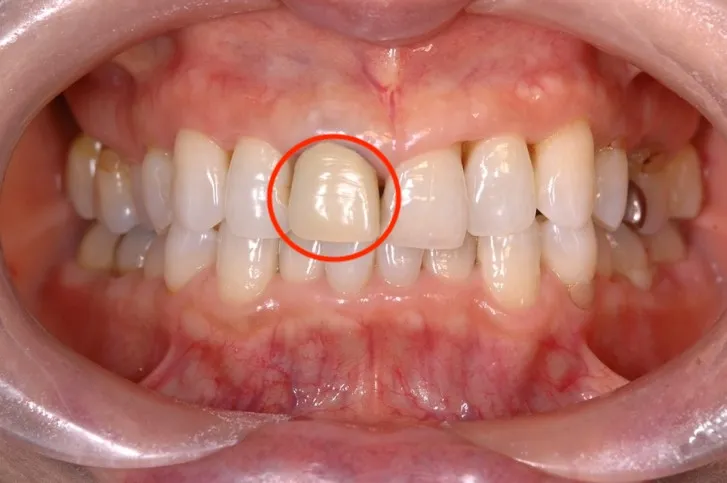

【治療前】

【治療後】